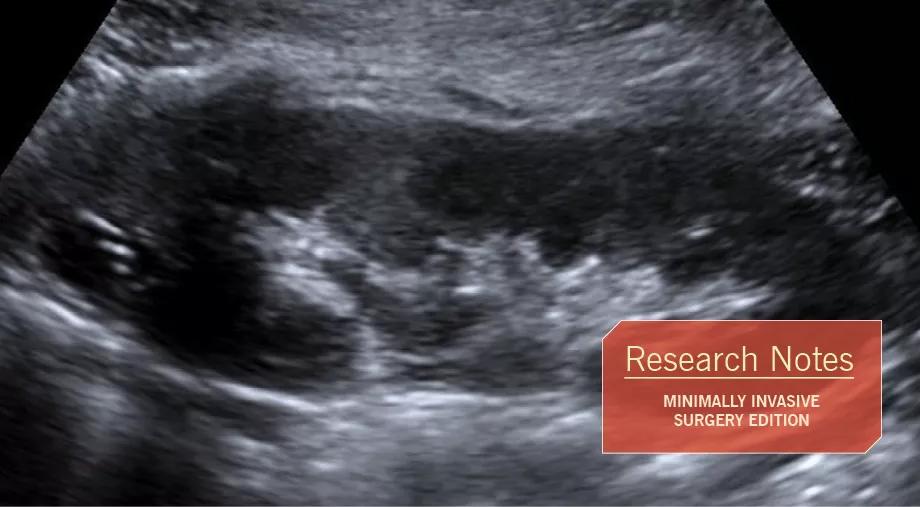

Figure 1. Preoperative ultrasound of the left kidney, sagittal view, showing a 1.6 x 1.1 x 0.9 cm cystic lesion in the upper pole. There is increased echogenicity within the periphery which may reflect calcifications.